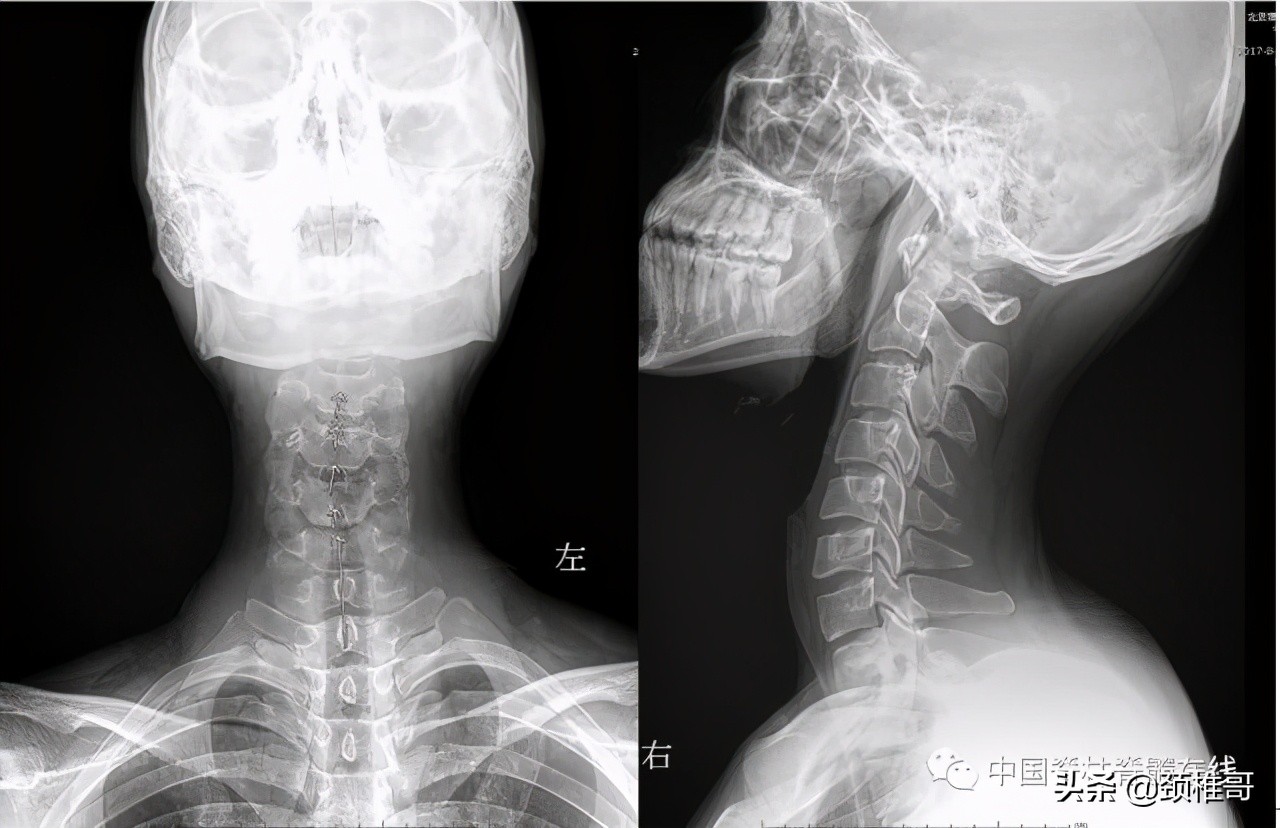

再看看这个病人,头晕2年,转头、低头时头晕加重,他的核磁共振显示椎间盘退变,水分减少了,但是没有明显的椎间盘突出,充其量算是膨出,但是我们看看他的x线片:颈椎3-5棘突序列不整齐,侧位显示颈椎5/6之间夹角增大,过伸位片显示,颈椎4-7各个节段夹角都超过了11°。过屈侧位片显示5、6、7三个节段出现了双边征,是椎体发生了旋转不稳的结果。这个病例的主要问题在于椎间盘吗?不对,在于肌肉和韧带对于颈椎4-7各个节段之间的稳定控制能力的减退。

正位:颈椎序列欠佳 侧位:颈椎4-7夹角增大

对节段颈椎成角过大、双边征

MRI显示颈椎多节段椎间盘退变膨出